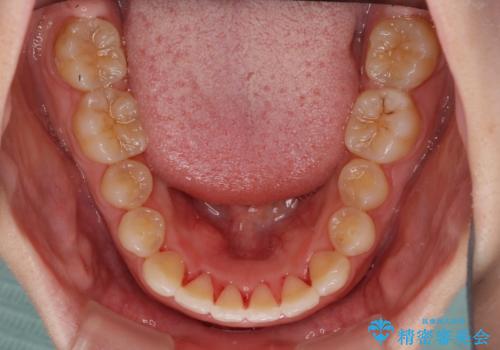

- 前歯のデコボコを治したいとのことで来院された患者様です。

上下顎ともに歯列全体の側方拡大とIPR(歯と歯の間を削る)によってデコボコが解消するように設計し、インビザラインにより治療を行うこととしました。

後方移動に際し、残っていた上顎の親知らずを抜歯することとしました。